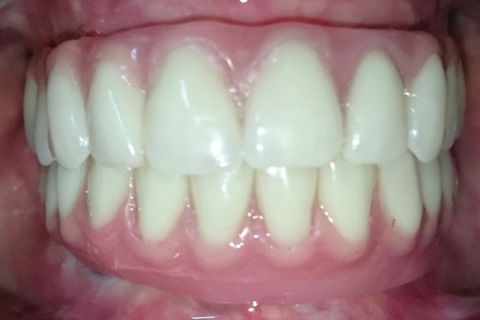

Dia da entrega daspróteses

Aspecto final de frente

Paciente masculino, 50 anos, desdentado total. Optou por reabilir-se com próteses sobre implante. Carga tardia.